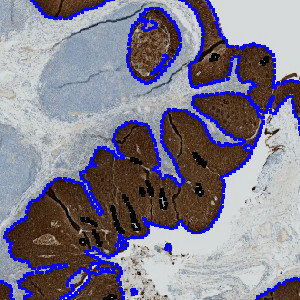

Figure 3

Illustration of the tissue alignment workflow linking the two differently stained serial sections together. This workflow requires the module Tissuealign™ with VirtualDoubleStaining™.

Figure 4

Tumor regions are automatically identified on the CK5 slide, and outlined with a blue ROI.